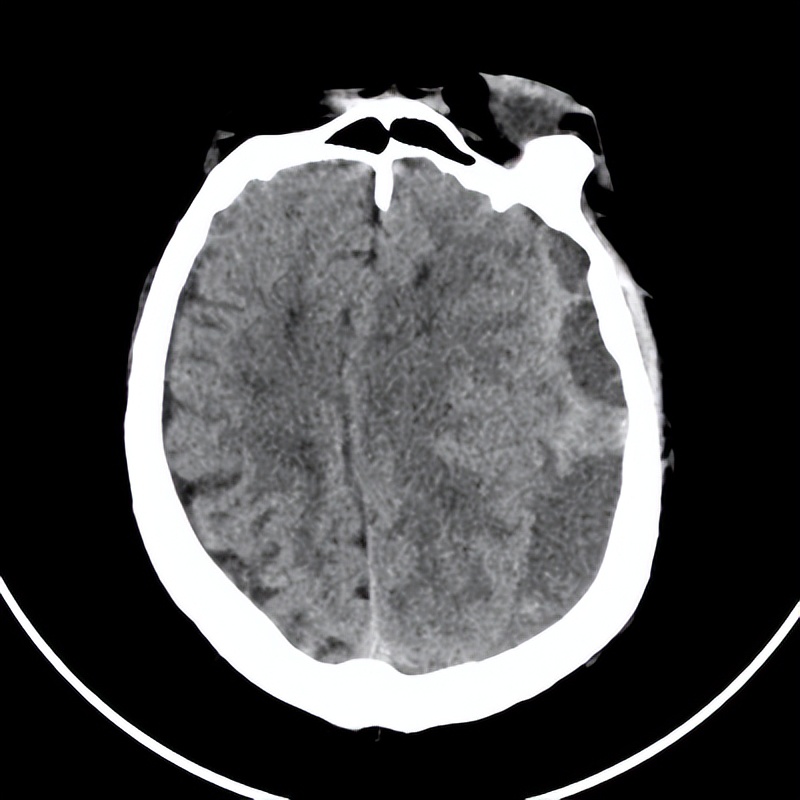

赵先生带着67岁的父亲赵大爷慕名来到哈医大一院神经外科五病房副主任梁洪生教授的诊室。起因两个月前,赵大爷不慎摔伤头部,当时没有重视。就诊前赵大爷出现走路不稳、情绪暴躁,来到医院检查发现左额颞顶枕硬膜下血肿,血量约100ml。赵大爷的儿子紧急找到梁洪生教授寻求帮助。入院以后,梁教授经过详细了解病史、查体、检查后,确诊赵大爷为慢性硬膜下血肿。

图一:左额颞顶枕硬膜下血肿

梁洪生教授表示:慢性硬膜下血肿是一种较常见的疾病。常规的治疗方法有药物治疗、钻孔引流术,对于一般患者来说治疗效果尚可,偶有复发。但赵大爷的硬膜下血肿波及范围较广,左侧额、颞、顶、枕部均有累及、呈分隔状,药物或单纯钻孔都无法快速彻底清除,并且病人已经出现半球受压征象、肢体瘫痪症状,近三个月出现脑梗的病史,术后护理困难,建议选择神经内镜对血肿一次性清除。梁洪生教授与赵先生沟通时提到:医生可以通过神经内镜利用小骨窗即可实现广泛血肿的清除,重要是在内镜直视下,可以确定出血点,是否有血肿残留等,具有创伤小、出血少、恢复快的优点。赵先生表示完全理解并认可这个治疗方案。